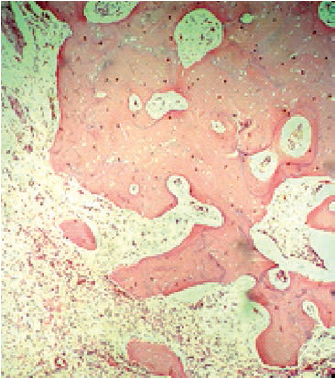

El procedimiento se realizó el 30 de marzo de 2016. El espécimen extraído se envió al Departamento de Patología del HUSI, que confirmó el diagnóstico histopatológico previo al procedimiento, de osteosarcoma fibroblástico de bajo grado, donde se evidenciaba un patrón celular fusiforme y fibroblástico, con matriz osteoide (figuras 4, 5, 6, 7). En este caso, el Departamento de Patología consideró que los estudios de inmunohistoquímica no eran necesarios.

El osteosarcoma mandibular puede imitar clínica y radiológicamente tumores benignos de crecimiento lento, en particular el osteosarcoma de bajo grado. De acuerdo con la clasificación de la Organización Mundial de la Salud del 2002, el diagnóstico de osteosarcoma mandibular se basa en la identificación de osteoide o hueso, producido por las células osteoblásticas tumorales. El osteosarcoma se puede clasificar en tres grupos: de bajo grado (paraosteal o central), de grado intermedio (periostio) y de alto grado (convencional, telangiectásicas y de células pequeñas) [5].

Los subgrupos histológicos convencionales incluyen un patrón osteoblástico, condroblástico y fibroblástico, definido de acuerdo con la abundancia y naturaleza de la matriz producida por las células tumorales. El más común aparece en la mandíbula, el patrón condroblástico, cercano a un 50 % de todos los casos [3,4,5,6].